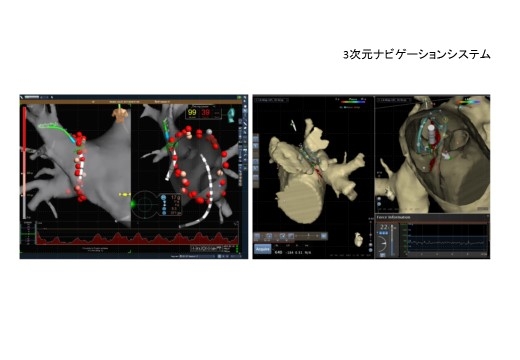

心房細動のカテーテルアブレーションも積極的に行っており、現在までに1,500例を超える手術件数となっております。また、2010年から3次元ナビゲーションシステムと先端電極冷却機能付きアブレーション・システム(イリゲーション・システム)を導入しました。2014年からはコンタクトフォーカス感知機能付きアブレーションカテーテルを導入しています。2015年、従来の高周波カテーテルアブレーションに加えて、冷凍凝固バルーンカテーテルアブレーションによる心房細動治療を開始しました。

3次元ナビゲーションシステム(EnSite / CARTO)

カテーテルアブレーション治療を行う際に、不整脈回路を3次元的にカラー表示することができ、従来の方法では困難であった複雑な不整脈回路の診断を可能とします。また、治療用アブレーションカテーテルが、心臓のどの部位に位置するか3次的に表示できるため、正確かつ効率的に治療を進めることができます。さらに、カテーテルと心臓との接触の方向や強さの情報も表示されるため、治療精度と安全性がより確実なものになっています。レントゲンを用いることなくカテーテルの位置が分かるので、手術に伴う患者さんや術者のレントゲン被爆を最低限に軽減する効果もあります。